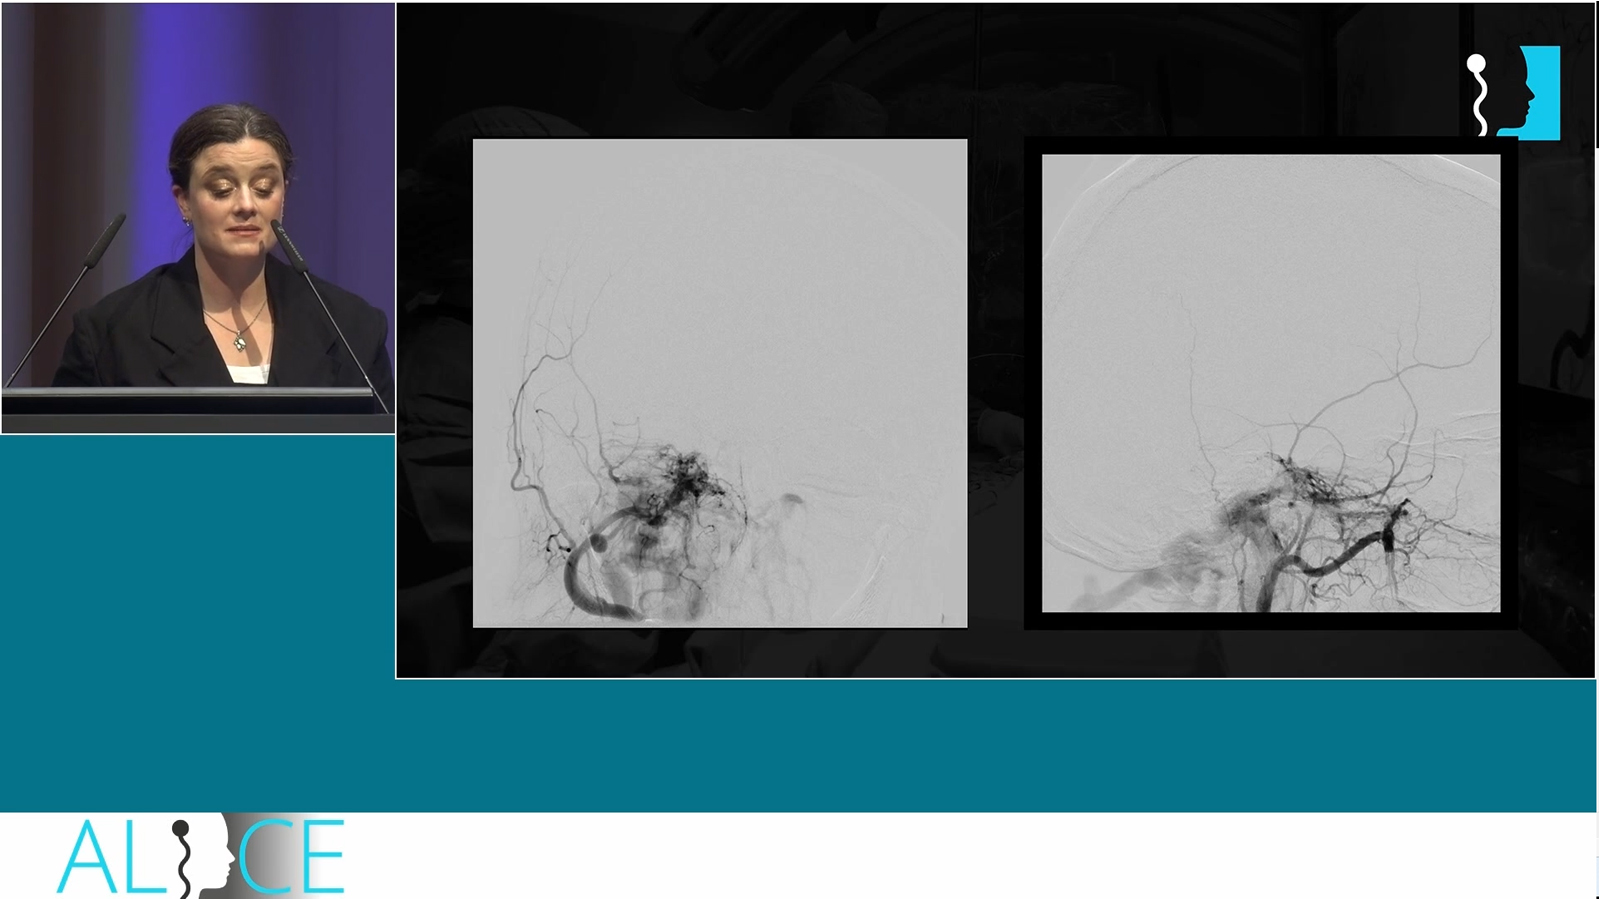

Acute ruptured dural fistula of the superior petrous sinus treated by transvenous embolization